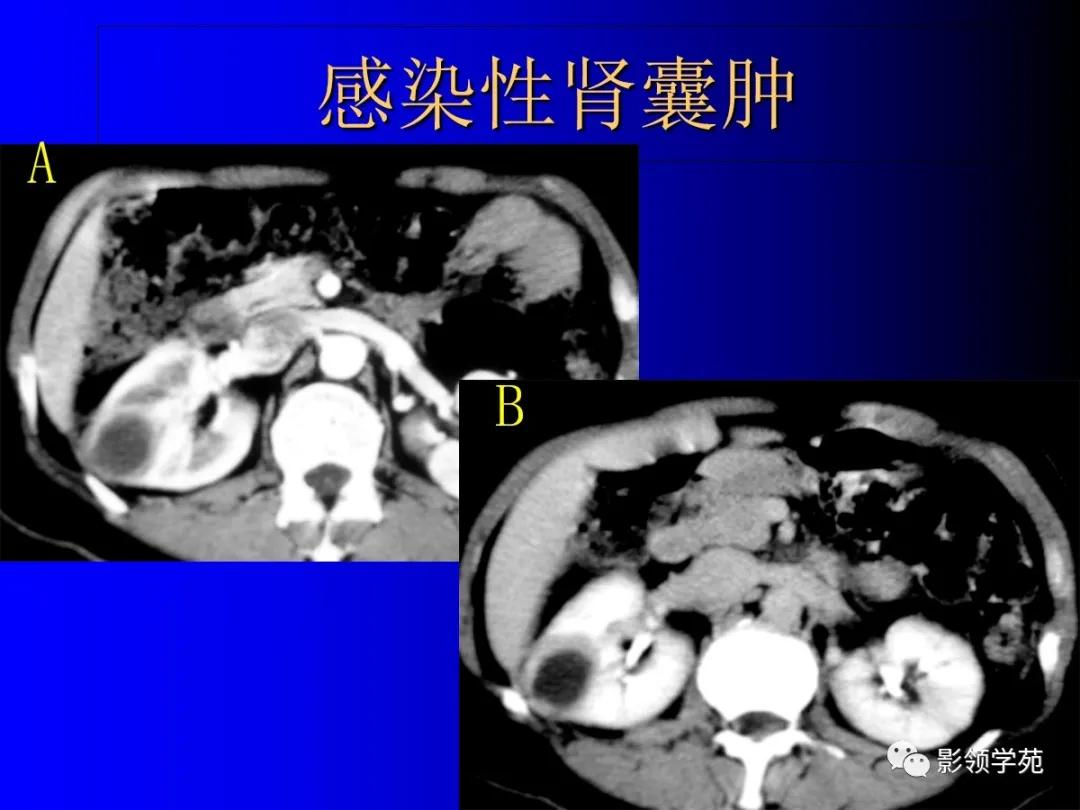

2、复杂性肾囊肿(Complicated cysts)

肾囊肿内含有血液、脓液、间隔或钙化

感染性囊肿。